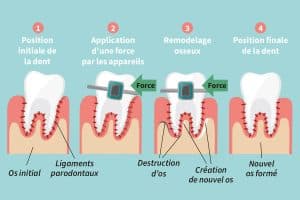

Nos dents tiennent en place dans notre mâchoire grâce à de petits ligaments. « Ce sont sur ces ligaments, d’une épaisseur de 0,2 millimètre, qu’on vient agir lors du traitement, explique le Dr Normand Bach. Par exemple, pour refermer un espace entre deux dents, la force appliquée par l’appareil va comprimer les ligaments d’un côté et les étirer de l’autre. »

Cette tension dans le ligament parodontal affecte les cellules osseuses de la mâchoire : les ostéoclastes, qui détruisent l’os d’un côté, et les ostéoblastes, qui fabriquent de l’os de l’autre côté.

« Ces cellules font le travail selon les forces appliquées par les appareils. Nous, les orthodontistes, on n’a aucun mérite ! » dit le professeur en riant.

En effet, si les dents nous paraissent dures et fixes, elles sont retenues en place sous nos gencives par tout un réseau de ligaments et de tissus « élastiques » (voir encadré). Après tout, c’est justement parce que les dents peuvent bouger qu’on est en mesure de réaliser des traitements orthodontiques…